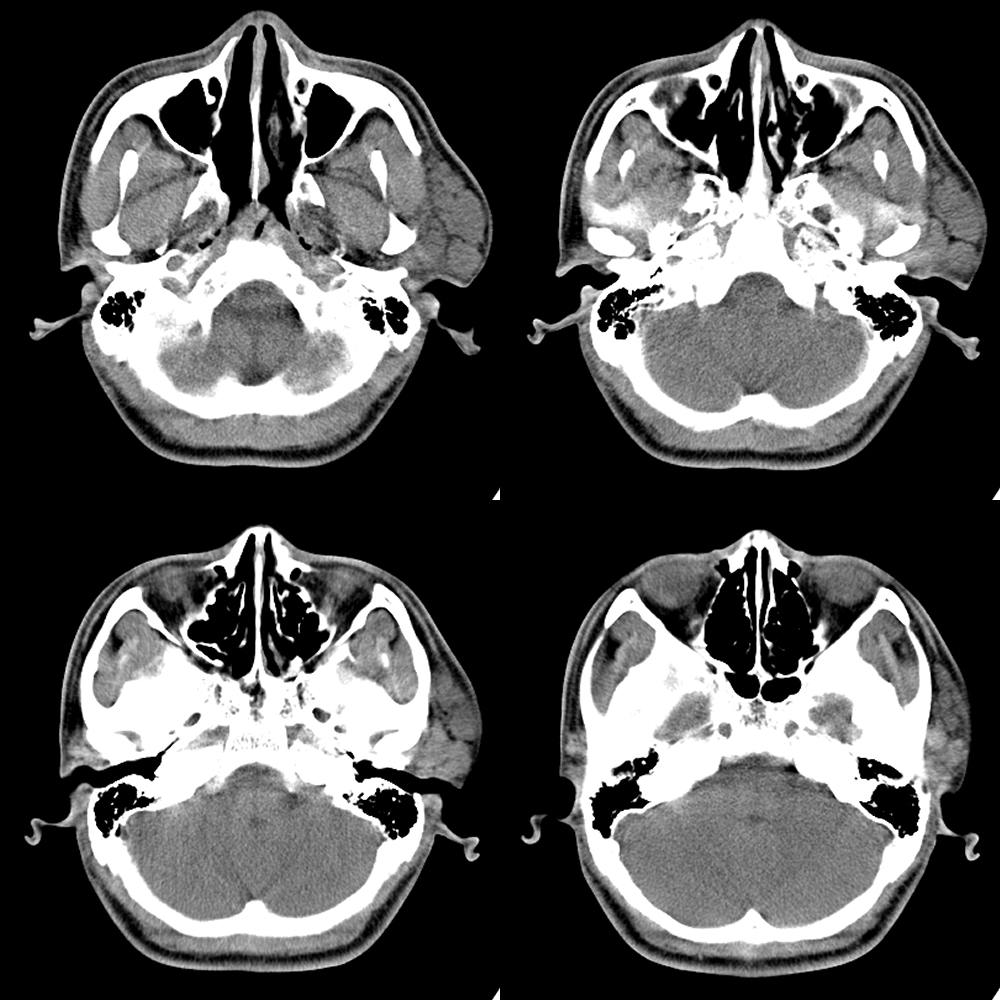

标题: CT14030:M17Y,腮旁肿块。

患者婴儿时期左腮旁有一1cm的隆起小包,缓慢张大,三岁时抽取为含气泡的黄色脓液,后治愈。今患者17岁时在一夜之间左腮旁隆起一较大、质软、无痛性肿块,在外院抽取600ml血性液体后包块仅轻度减小。经患者同意后手机拍照:

病灶ct值为52hu。